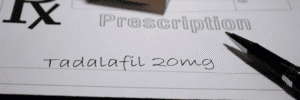

Lupron is a medication that belongs to a class of drugs known as gonadotropin-releasing hormone (GnRH) agonists. It works by significantly reducing the body’s production of testosterone, a hormone that prostate cancer cells often rely on for growth. Administered through injections, either monthly or every few months, Lupron is commonly used in the treatment of prostate cancer, particularly in advanced or metastatic cases.

Lupron works through androgen deprivation therapy (ADT). Initially, it causes a temporary surge in testosterone levels, but after a few weeks, it leads to a significant reduction. This drop in testosterone levels helps slow or stop the development of prostate cancer. Lupron can be used as a first-line treatment for advanced prostate cancer or as part of a combination therapy with other treatments like radiation or chemotherapy to improve their effectiveness.

Lupron is highly effective in managing prostate cancer, especially in advanced stages. However, over time, some patients may develop castration-resistant prostate cancer (CRPC), a condition where the cancer becomes less responsive to hormone therapy. In these cases, additional therapies like chemotherapy or newer targeted treatments may be required.